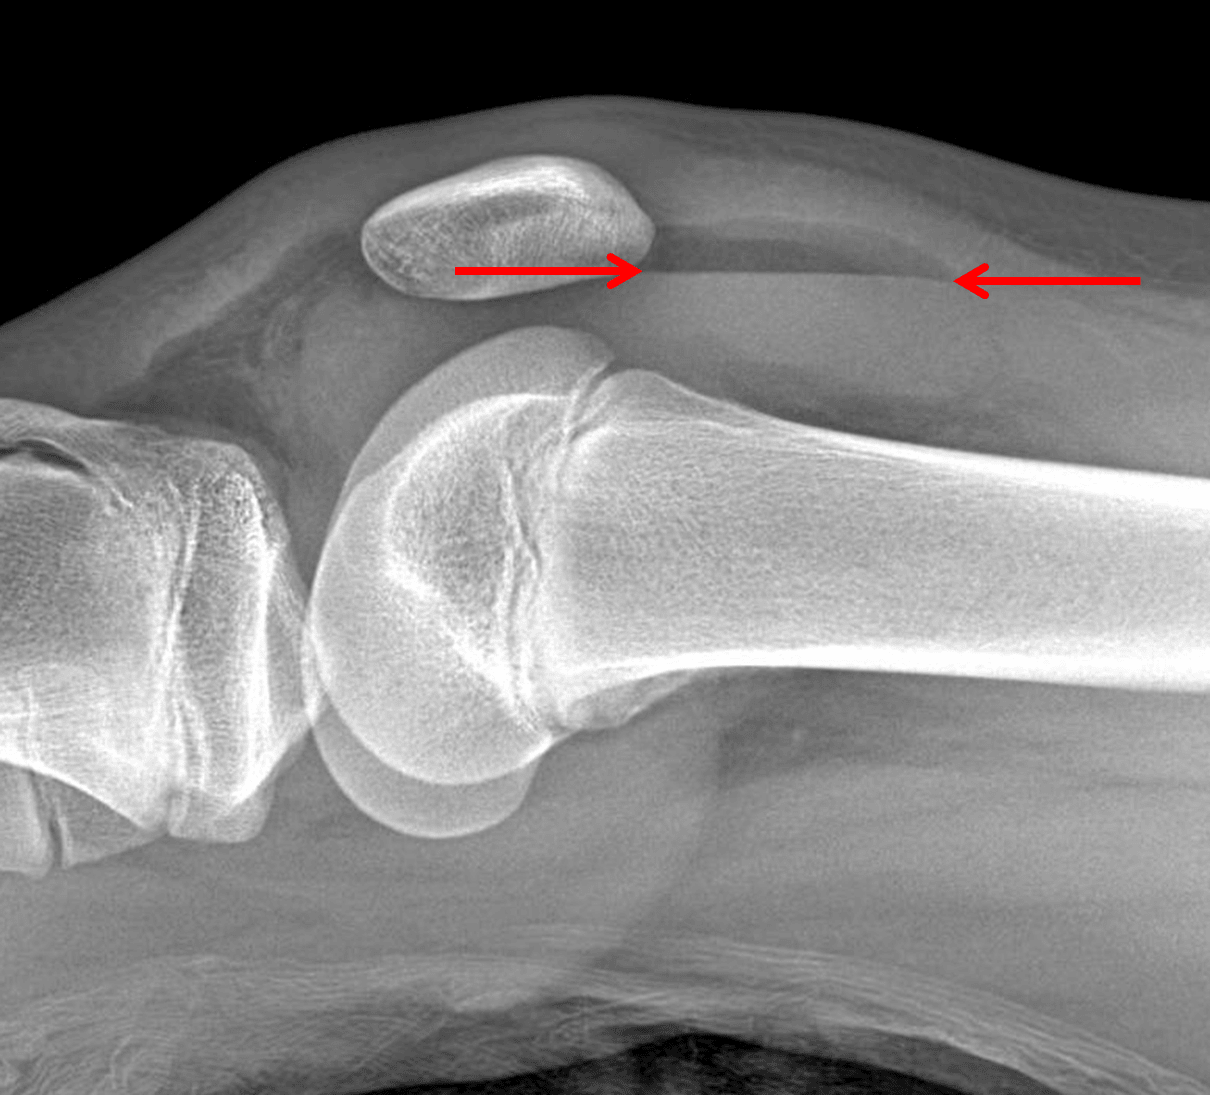

• Look for a layering fat-fluid level on cross table lateral view

Red arrows: fat fluid level indicating a lipohemarthrosis.